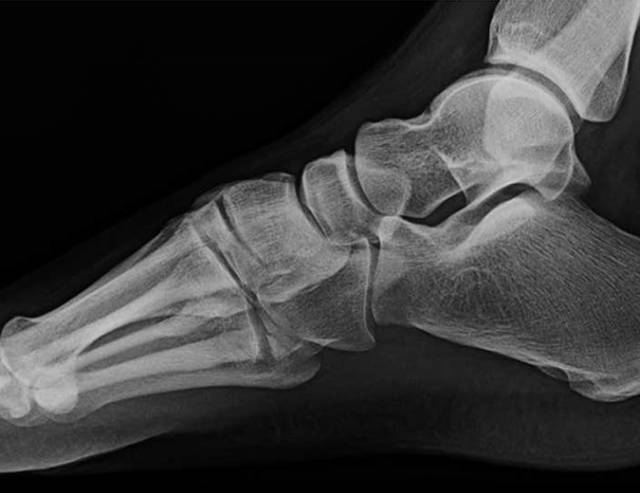

在脚踝处,必须警惕超出投照视野(图4)的足部腓骨骨折的可能性和足部骨折的可能性。例如,Maisonneuve骨折是一种旋前 - 旋转损伤,伴有远端胫腓骨间继位断裂和近端腓骨骨折[19]。了解骨折模式与相关的损伤机制模式至关重要,特别是在踝关节[20]。

图。4A-28岁女子在地面跌倒后。A,踝关节的斜视图显示继发性加宽和微小的内侧踝撕裂性骨折。B,近侧腿的侧视图显示倾斜的近端腓骨骨折,构成Maisonneuve骨折。